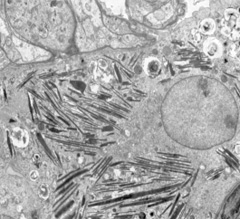

结果展示